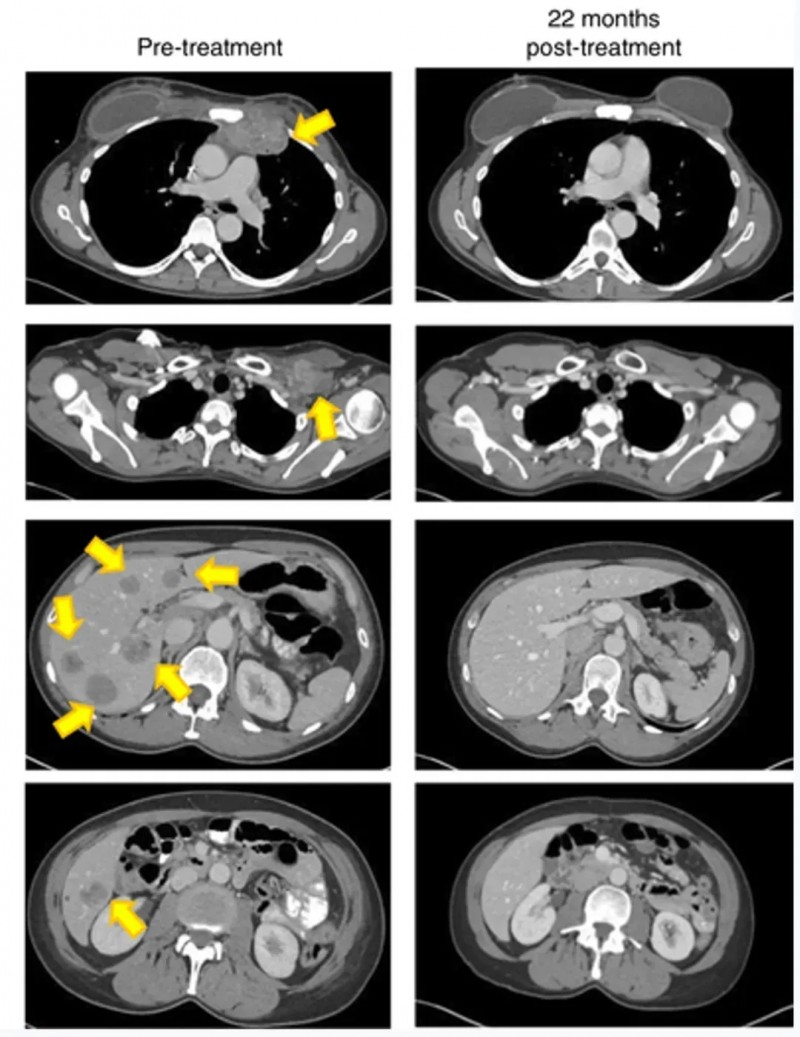

患者1是一位49岁男性,因肝细胞癌破裂入院。上腹部CT显示左肝叶多发病灶(最大病灶71×48mm),左侧门静脉充满肿瘤血栓;肺部CT发现多个结节。甲胎蛋白水平超60,500ng/mL,确诊为乙型肝炎病毒(HBV)相关性肝细胞癌,BCLC分期为C期。

患者入组I期临床试验(NCT03658785)后,先接受左半肝切除术,并获取肿瘤组织用于TIL培养。之后相继接受淋巴细胞清除方案(环磷酰胺+氟达拉滨)、TIL细胞回输治疗、白细胞介素-2(IL-2)治疗、两次托利普利单抗注射治疗。

结果显示:肝切除术后2个月,所有肺转移灶完全消失,至今(48个月)仍保持无瘤状态(详见下图a、b)。

▲图源“Liver Cancer”,版权归原作者所有,如无意中侵犯了知识产权,请联系我们删除

患者2

患者2是一位67岁女性,因肿瘤破裂出血接受经肝动脉栓塞术后1周入院。CT显示肝左叶147×79mm混合信号肿块,双肺存在多个散在结节,右肺中叶最大结节直径18mm。甲胎蛋白水平14,529ng/mL,确诊为HBV相关性肝细胞癌,BCLC分期为C期。

该患者入组后,接受了姑息性左半肝切除术,在TIL培养29天后,先后接受淋巴细胞清除治疗+自体TIL细胞单次输注+IL-2治疗+特瑞普利单抗治疗(18个疗程)。

结果显示:肝切除术后1个月,肺转移灶进展,右肺结节增大至25mm;接受TIL输注及常规抗PD-1治疗后,术后10个月肺病灶完全消失,至今24个月仍保持无瘤状态(详见下图c、d)。